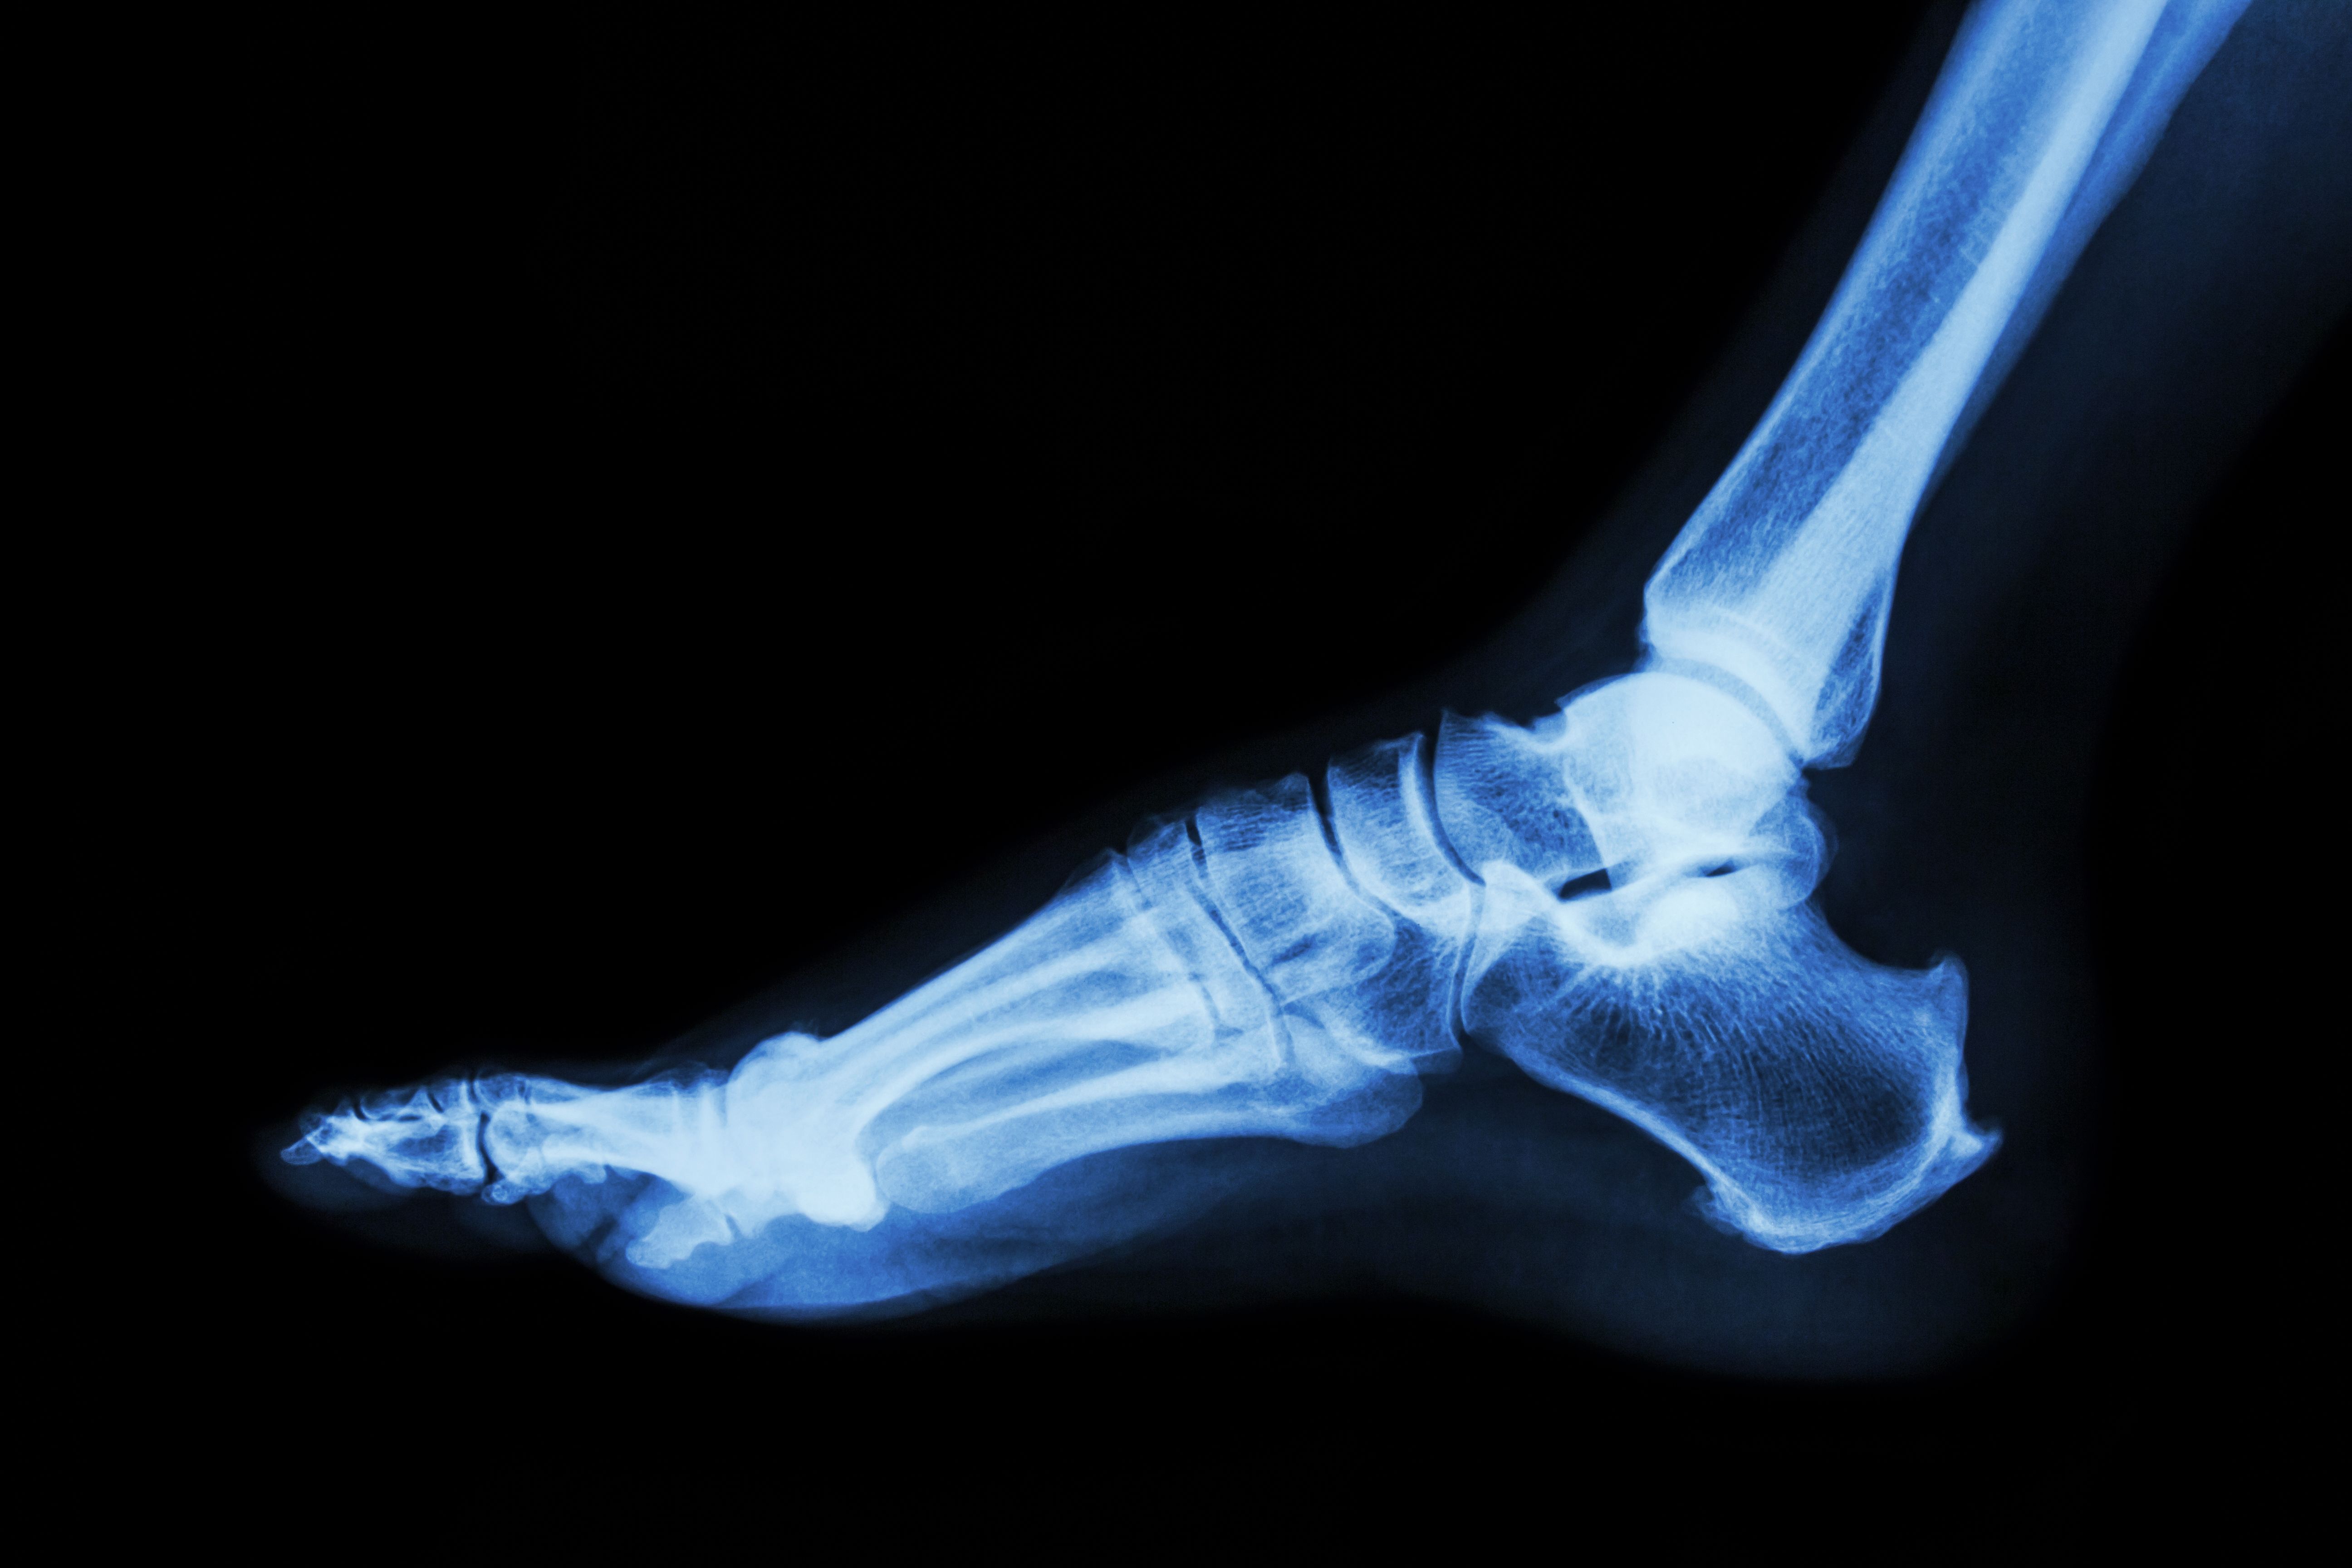

The process of undergoing ankle surgery involves several stages. Initially, thorough diagnostic tests such as X-rays or MRIs are conducted to determine the exact nature of the problem. Post-diagnosis, discussions with your surgeon will cover the surgical options available to you. This is an ideal time to ask any questions and express any concerns you may have regarding the procedure.